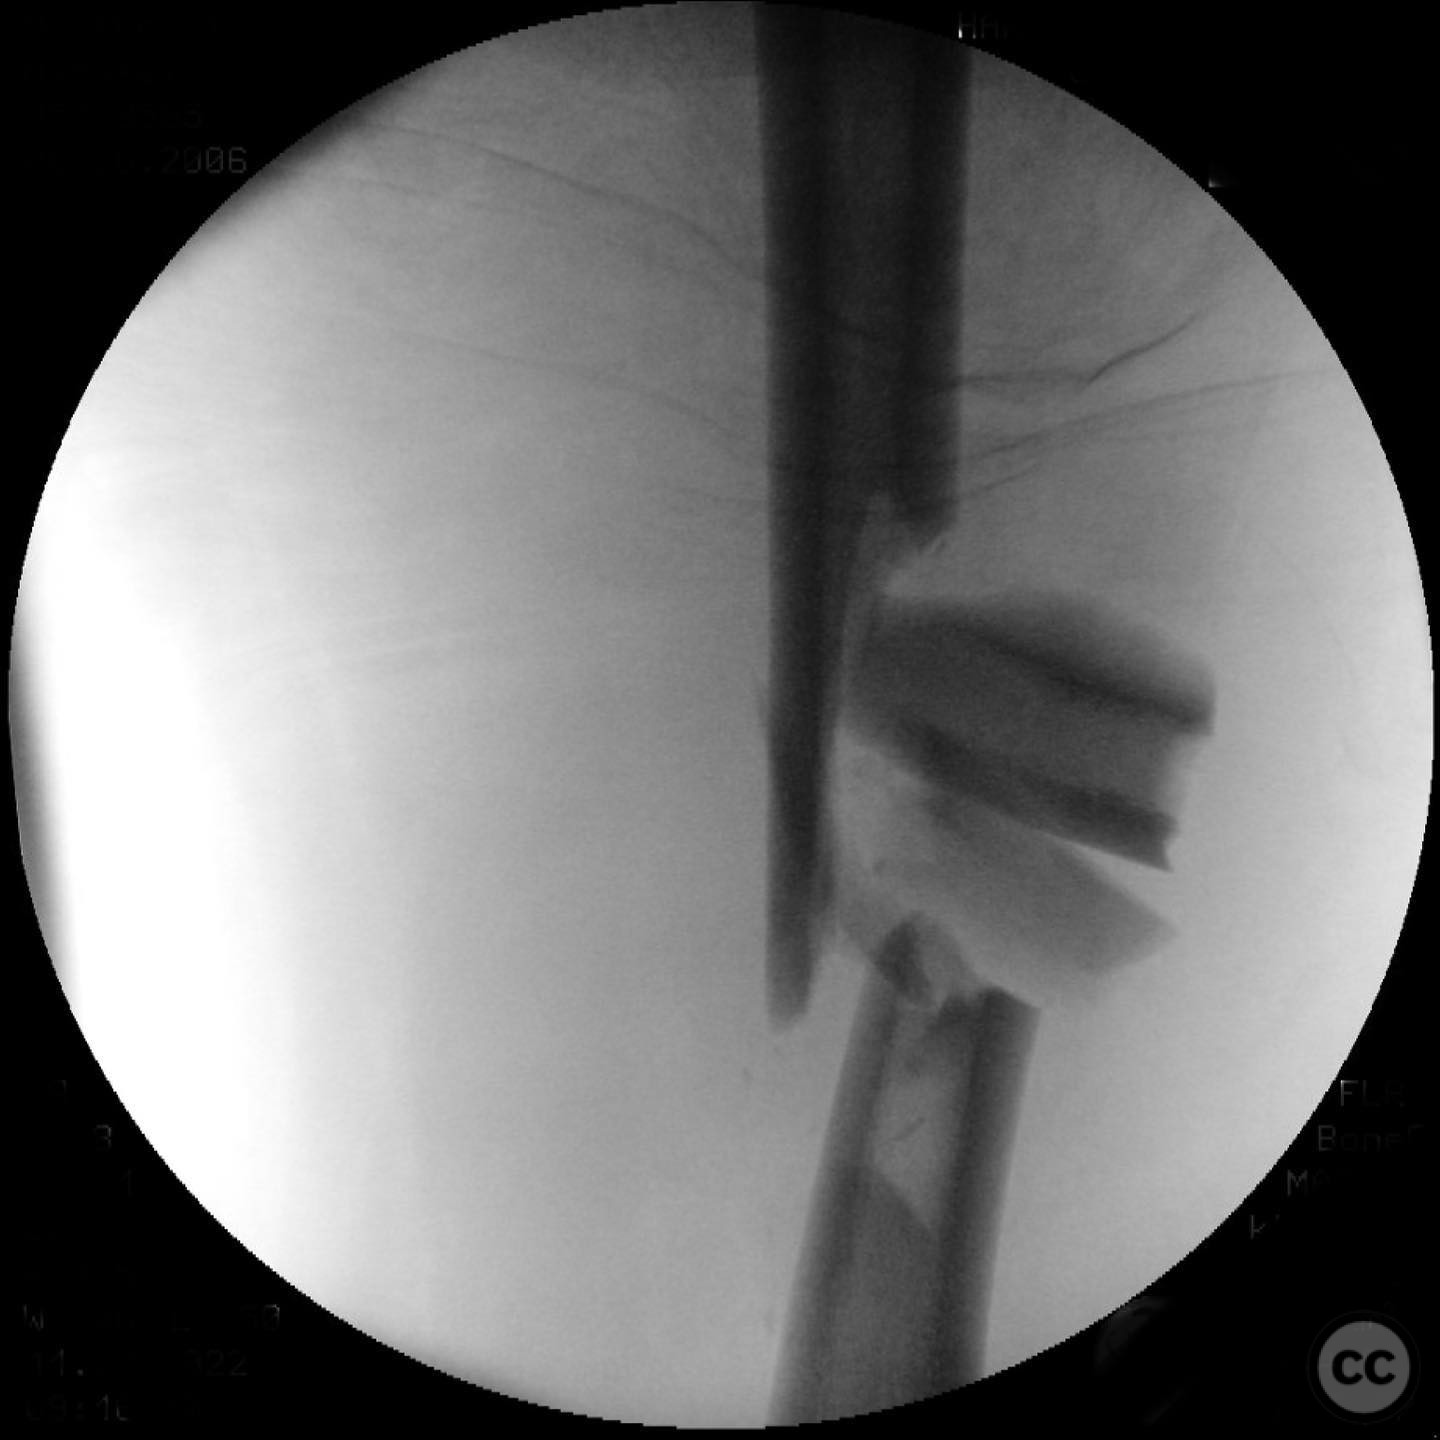

Patient positioning:  The patient was positioned supine on a radiolucent table to facilitate intraoperative imaging and access to the femur.

Anatomical surgical approach:  A lateral approach to the femur was performed, involving an incision along the lateral aspect of the thigh. Subperiosteal dissection was carried out to expose the fracture site while preserving as much periosteum as possible. Care was taken not to disturb the medullary hematoma, and reamings were collected for later use in grafting.

Operative remarks:

The surgeon noted that indirect reduction techniques were inadequate due to the fracture's complexity, necessitating an open reduction. Emphasis was placed on preserving fracture biology by minimizing periosteal stripping and avoiding suctioning of the medullary hematoma. Reamings were used as autograft material around the fracture site to enhance healing.